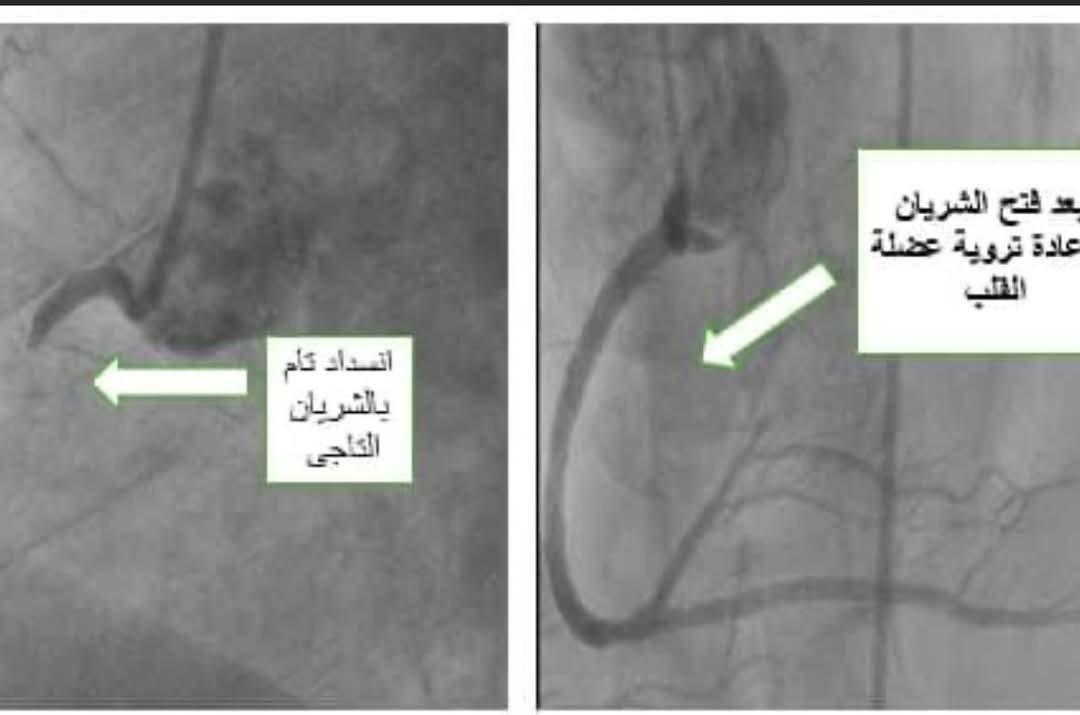

إذ حضر إلى قسم الطوارئ بمستشفى بني سويف التخصصي مريضًا في العقد الثالث من العمر، يعاني من عدم القدرة على التنفس، وألم شديد في الصدر، وعقب خضوعه للفحوصات اللازمة، والتي تضمنت إجراء رسم قلب، وتحليل إنزيمات القلب)، تبين إصابته بجلطة حادة في شرايين القلب يصحبها بتباطؤ في نبضات القلب.

وقام الفريق الطبي على الفور بنقل المريض إلى قسم قسطرة القلب، حيث تم إجراء عملية قسطرة قلب عاجلة له، وجرى تركيب دعامة في الشريان الخلفي لإعادة تدفق الدم، مما أسهم في استعادة كفاءة القلب وانتظام ضرباته.